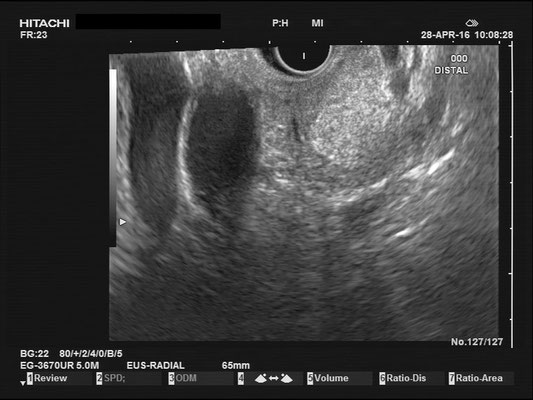

Normal findings - Pancreas / Common bile duct (CBD)

Pancreas

The images above depict a thorough inspection of the pancreas, as seen in an radial EUS Examination. We begin (hopefully ;) bei identifying the uncinate process between the golden V, which is formed by the aorta/V. cava and the mesenteric vessels. After spotting die usually hypoechoic ventral pancreatic root, the duodenal papilla can be identified (for a more detailed approach, please visit "Learning Endosono"). By following the splenic vein, the body and tail of the pancreas can be examined.

The most observant viewers will have noticed that not all images above depict normal findings but some abnormalities. (my bad ;)